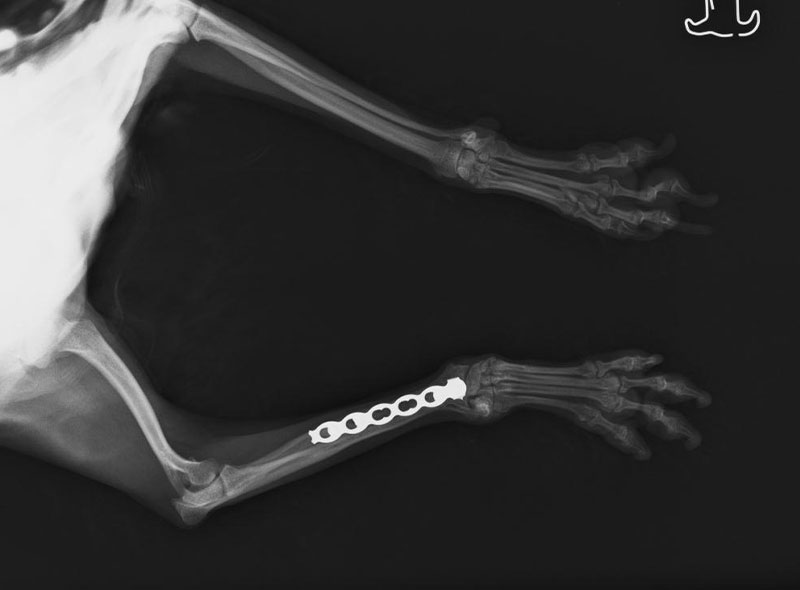

骨折

小型犬のこいぬは、はしゃぎすぎてどこかに前足を引っ掛けてしまい、骨折してしまうことがあります。その他、高所からの落下(抱き上げた高さでも)、猫では、中途半端な高さからの落下による着地不良、交通事故により骨折をすることがあります。

動物の動きを制御しにくい場合は、まわりの安全を考えた環境づくりをしてみましょう。

※写真は、2kgトイ・プードルの骨折

この子は、小さい時に右前足の骨折、今回は、抱き上げた高さからの落下で、指の骨を骨折しています。